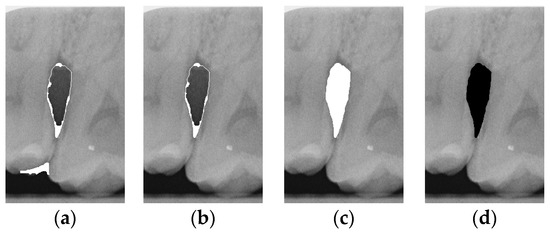

To ensure that only the area framing the symptom is preserved, and to remove the rest of the interfering areas or lines, the symptom frames are extracted according to the closure algorithm, i.e., the maximum connectivity area can be preserved to remove the frames of the non-symptomatic areas, as shown in Figure 7b. After the closure process, some of the frame lines are less smooth than others, which may affect the discrimination accuracy. To deal with this situation, this study performs the filling of the frame lines at the symptom area to facilitate the training of the model. Black and white are chosen to highlight the contrast and to compare the difference in discrimination between the two fill colors, as shown in Figure 7c,d.

The third method employs morphological closing operations for image processing. Although the Canny algorithm can outline the edges of the teeth and eliminate noise, some noise remains unremoved, and the depicted edges are not continuous and complete, leading to inaccuracies in lesion depiction. Therefore, this study tests three different approaches to morphological closing: standard closing, closing with black fill, and closing with white fill. The results are shown in Table 10. However, after training, it is found that the effects of filling with black and white are not better than the original closing operation, and there is no significant improvement in validation accuracy. Thus, further exploration of different methods is needed to find a more suitable image processing approach.

Figure 7. Comparison of extracting the closed area and filling. (a) Close operation. (b) Extracting the closed area. (c) Filling with white. (d) Filling with black.